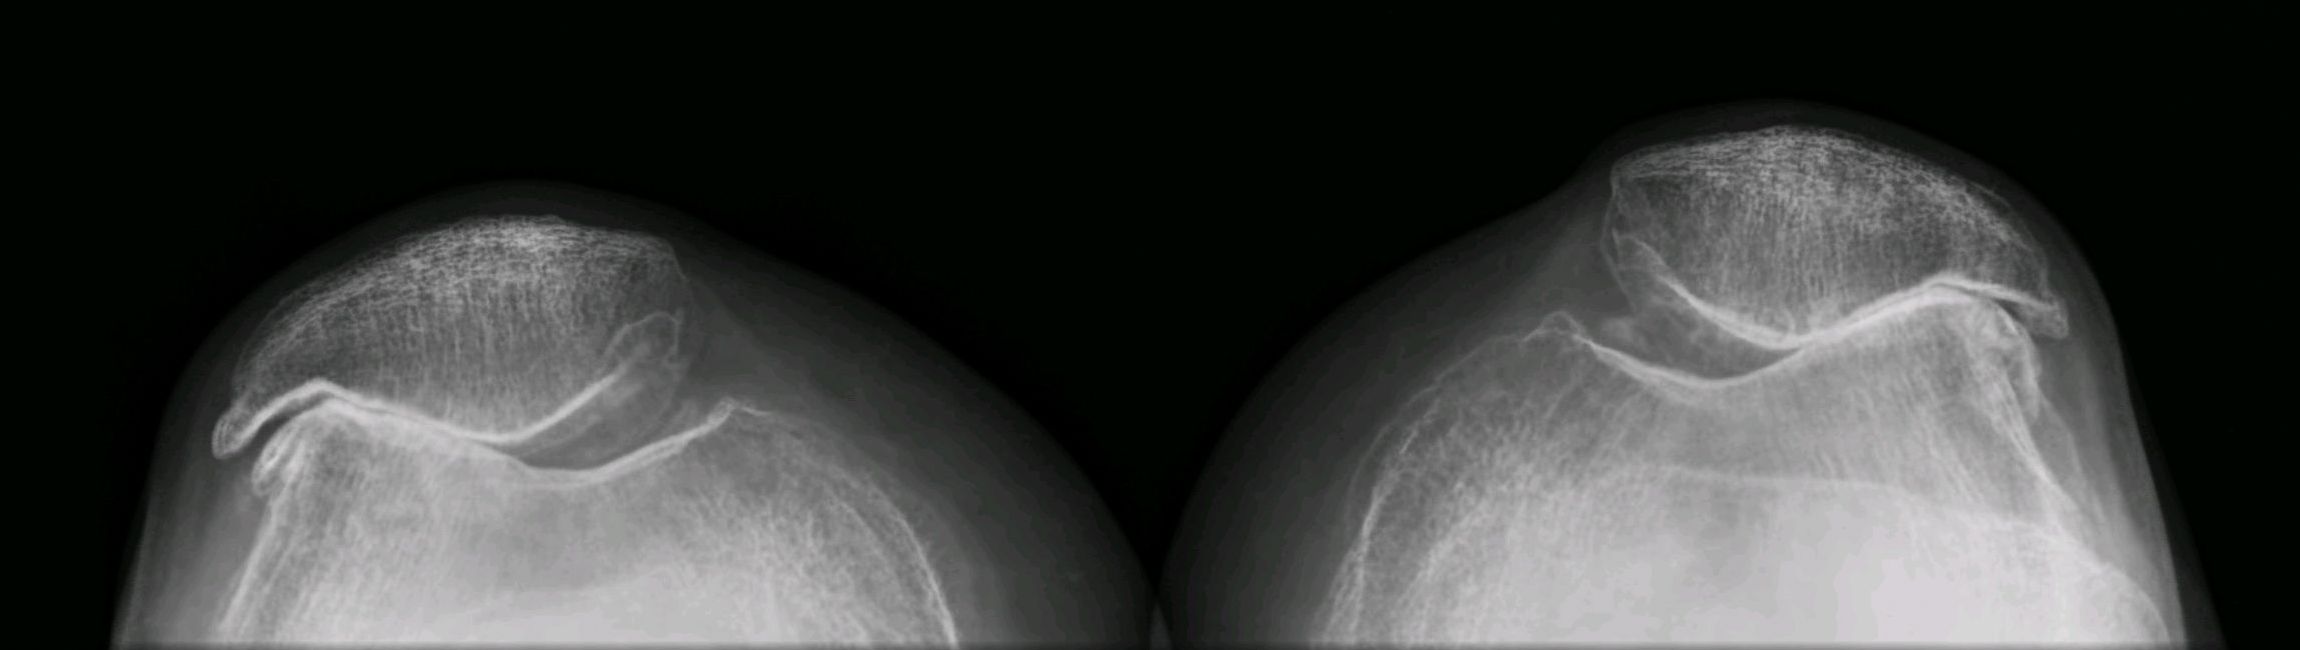

Severe 3

Severe 3 111 фотографий